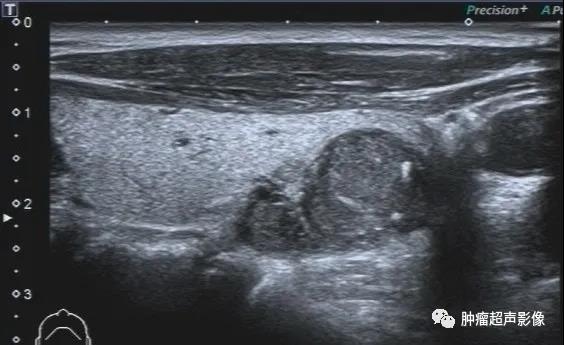

上图:甲状腺结节呈低回声,边缘不光整,纵横比大于1,内见点状强回声,可分到5类,内部无血流,

回顾以前检查可发现同一位置有一囊实性结节(下图),从而确诊皱缩结节,避免穿刺及手术。